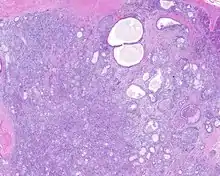

When reviewed by a pathologist, the findings are quite similar to fibrocystic changes of the breast, although they are different enough, that it is now recognized to actually represent a true neoplasm (clonal proliferation) through various studies.[5] Specifically, the lesions are usually well-circumscribed, containing lobules of haphazardly arranged ducts, myoepithelial cells, and acini that have abundant sclerosing or hyalinized fibrosis. Apocrine change is quite common in the ductal cells.[6] The ducts range from small ductules to cystically dilated spaces (more than 4 striated duct-widths across), often containing products of secretion or reactive histiocytes. A very curious and characteristic finding in all of the lesions is the presence of bright pink (eosinophilic) acinar granules (which are altered zymogen).